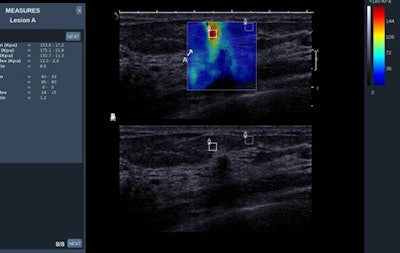

"Breast elastography is indeed helpful in providing further information about breast lesion stiffness, the point being that cancers are stiffer than benign lesions and lesions having a similar B-mode aspect could be further differentiated as benign or malignant according to their stiffness (i.e., their elastic value)," noted Dr. Alexandra Athanasiou, from the radiology department at the Institut Curie in Paris.

This clinical case is of a small infiltrating ductal carcinoma coded as red, i.e. elevated elasticity value. The resolution of the technique is 1 mm. Image courtesy of Dr. Alexandra Athanasiou.

This clinical case is of a small infiltrating ductal carcinoma coded as red, i.e. elevated elasticity value. The resolution of the technique is 1 mm. Image courtesy of Dr. Alexandra Athanasiou.Numerous studies have already been published to validate breast elastography, and further research is ongoing in order to define elastography criteria, she added. It's important to note breast ultrasound elastography will be part of the new edition of the BI-RADS lexicon for ultrasound.